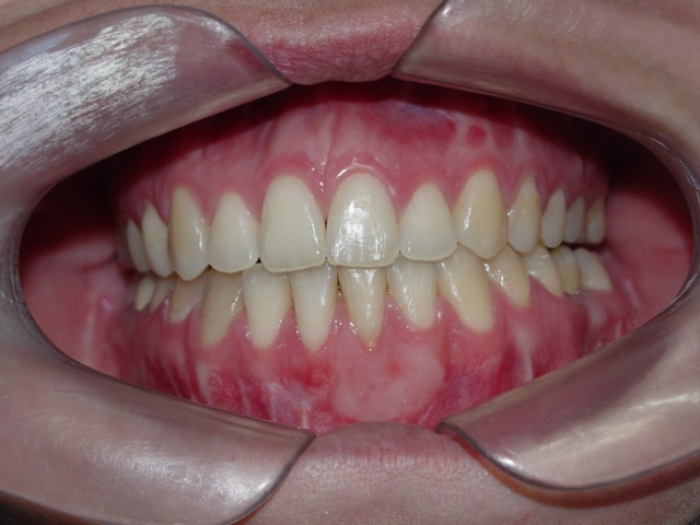

Mordida final